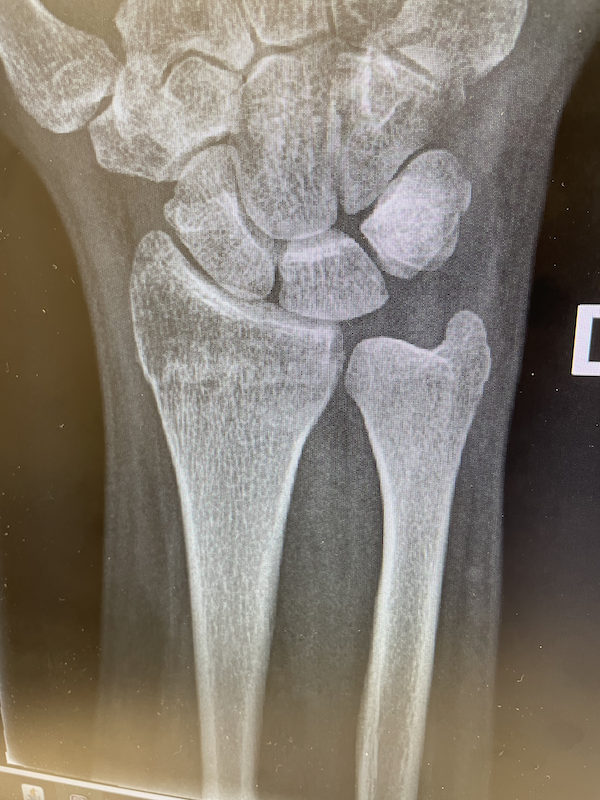

I broke a bone for the very first time on July 27, 2023. The tale of how I was betrayed by gravity and gifted a distal radius fracture is pretty silly, all things considered:

X-rays taken on September 6 2023 show that the bone is looking a lot less broken, but a lateral view shows that it hasn't yet finished putting itself back together yet, as there is still a rather large gap under my wrist.